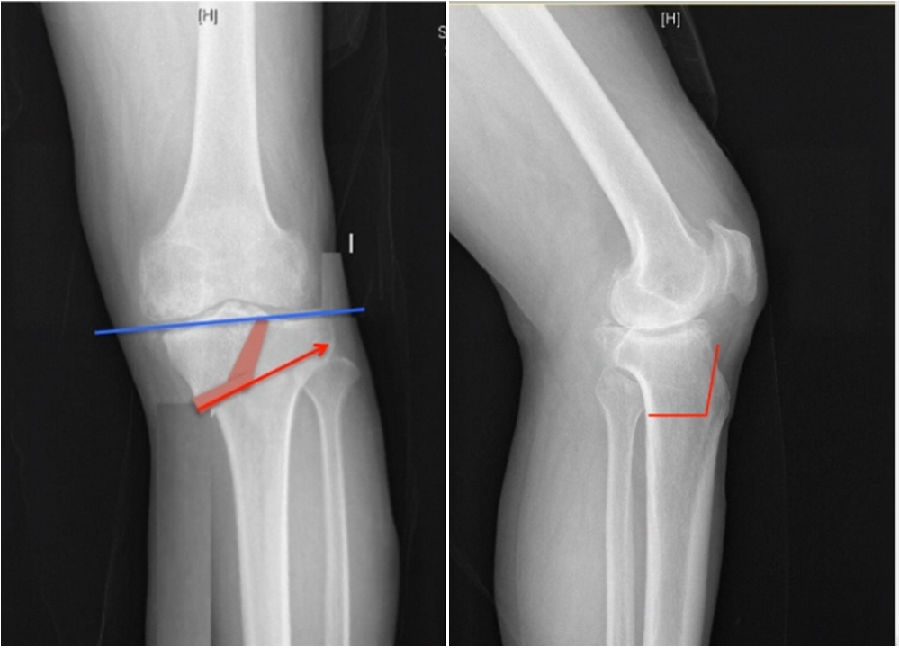

典型病例,女性,56岁,农民右膝内翻18度。

术前影像

结合影像学来看,该患者单纯用闭合截骨或开放截骨,对肢体均有影响,所以决定采用混合型截骨。术中混合截骨旋转中心选在内外1/3处,先做闭合楔,然后顺势将开放楔敲开,达到术前设计的目标力线。术后随访力线达到要求。